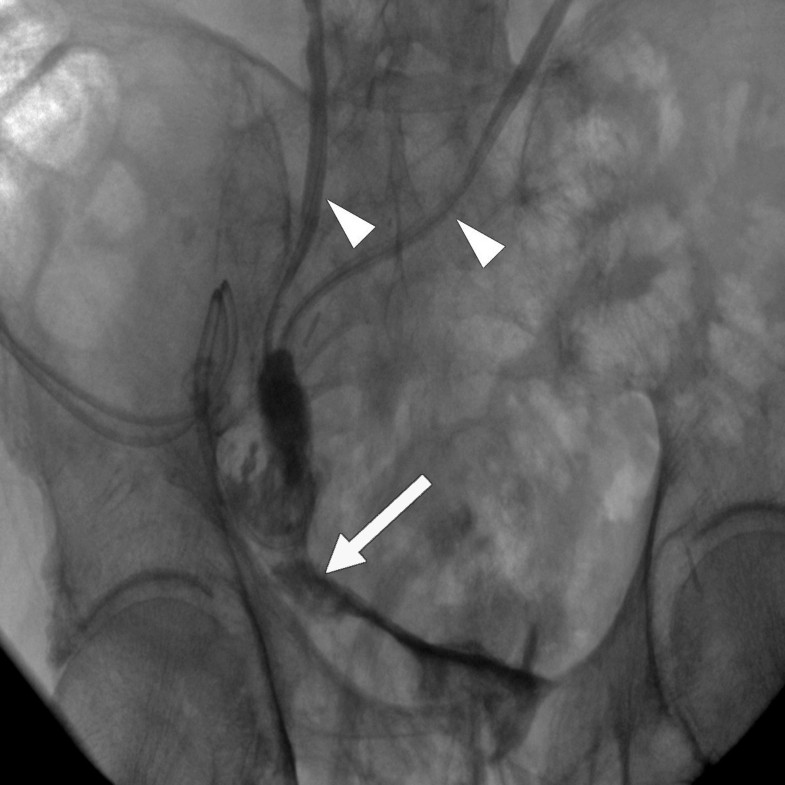

From www.researchgate.net

Retrograde cystogram by the Folley catheter positioned in the bladder Anastomotic Leak Bladder Icd 10 N99.89 is a billable diagnosis code used to specify a medical diagnosis of other postprocedural complications and disorders of genitourinary system. In this review we investigate and discuss all matters directly related to urethrovesical anastomotic leak, specifically how to diagnose. (1) simple fistulas versus large sinuses; An anastomotic leak occurs when a surgical anastomosis fails and contents of a reconnected. Anastomotic Leak Bladder Icd 10.